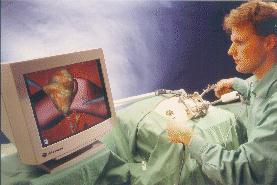

Once all of the preparation is complete, it is time to pass control to the robot for the actual implementation of the surgery.

The robots used for automated surgery tend, at the present time, to be adapted industrial robots; for example, the PUMA robot arm. The reasons behind this are predominantly financial ones. Investing in the research and development of a robot for a specific task is highly expensive - costs running into millions of pounds, with no guarantee that a suitable product will be the outcome. Another hurdle is the lack of official safety guidelines and standards. Having brought up the fact that the surgeon is reliant upon the engineering behind the tools that they are using, it is clear that companies would not wish to risk possible legal proceedings should one of their products fail. (These issues will be further discussed in the section on safety). As it stands, industrial robots are adequate for the tasks involved, although it is hoped (and expected) that, in the future, surgery- specific robots will be developed and will become an industry of their own. Once the robotic procedure is initiated, sensors collect real-time data from the operating site and pass this to a display, via which the surgeon observes the operation. The type of sensor that seems to best suit the surgical application is the use of infra-red transmitters on the robot's 'joints', that are detected by cameras in the operating theatre (currently under commercial development by General Electric). From these, the exact position of the robot's appendages can be gauged and relayed back to the surgeon's display. It is an issue as to what control a surgeon should have when overseeing an automated surgery - as they may do more damage than good if they intervene. The most common arrangement is to have a 'stop' switch and perhaps a 'redo' control. Sensing the patient, intra-surgically, is fairly simple when using fiducials (the fiducials are specially made from materials that are easily detectable under the system being used). This is not the case, however, when using the preferred surface techniques. Here a variety of systems are under consideration, including an ultrasound sensor or an x-ray sensor - both mounted on a 'C-arm' so that they can move around the whole area of the patient. |

Evaluation is an integral part of any surgical operation. In a robotic one, it is even more so since the surgeon did not have an opportunity to check everything before proceeding with the subsequent steps. If it is found that something is not completely satisfactory, then the surgeon has the option to either repeat the whole operation or to carry out a manual procedure to complete the work.